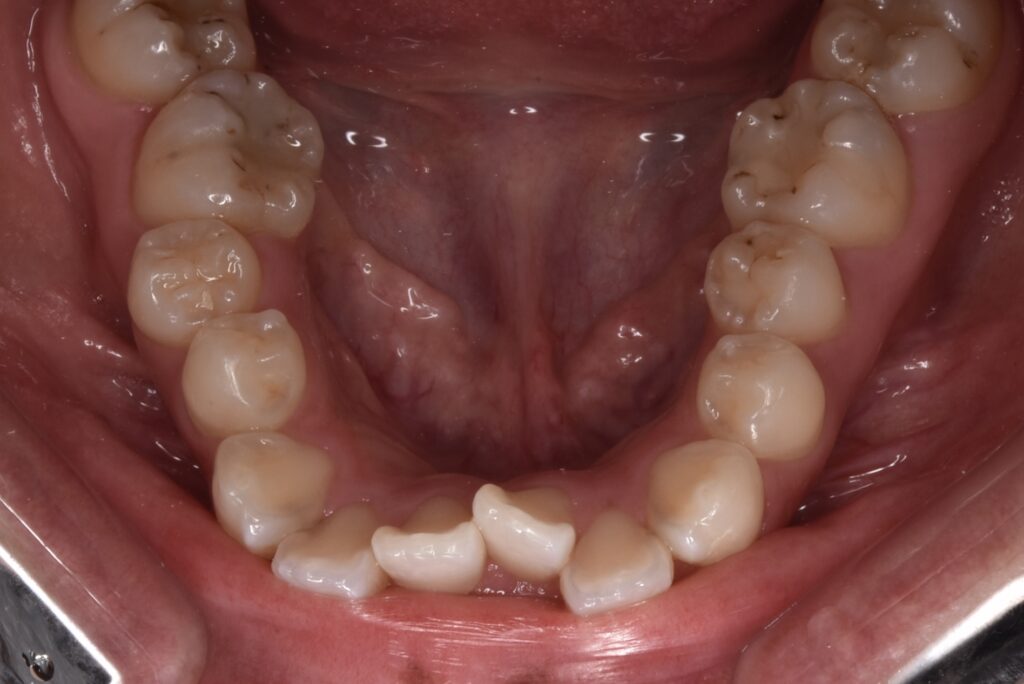

矯正前

前歯の突出感と下の歯の叢生が目立ちます。